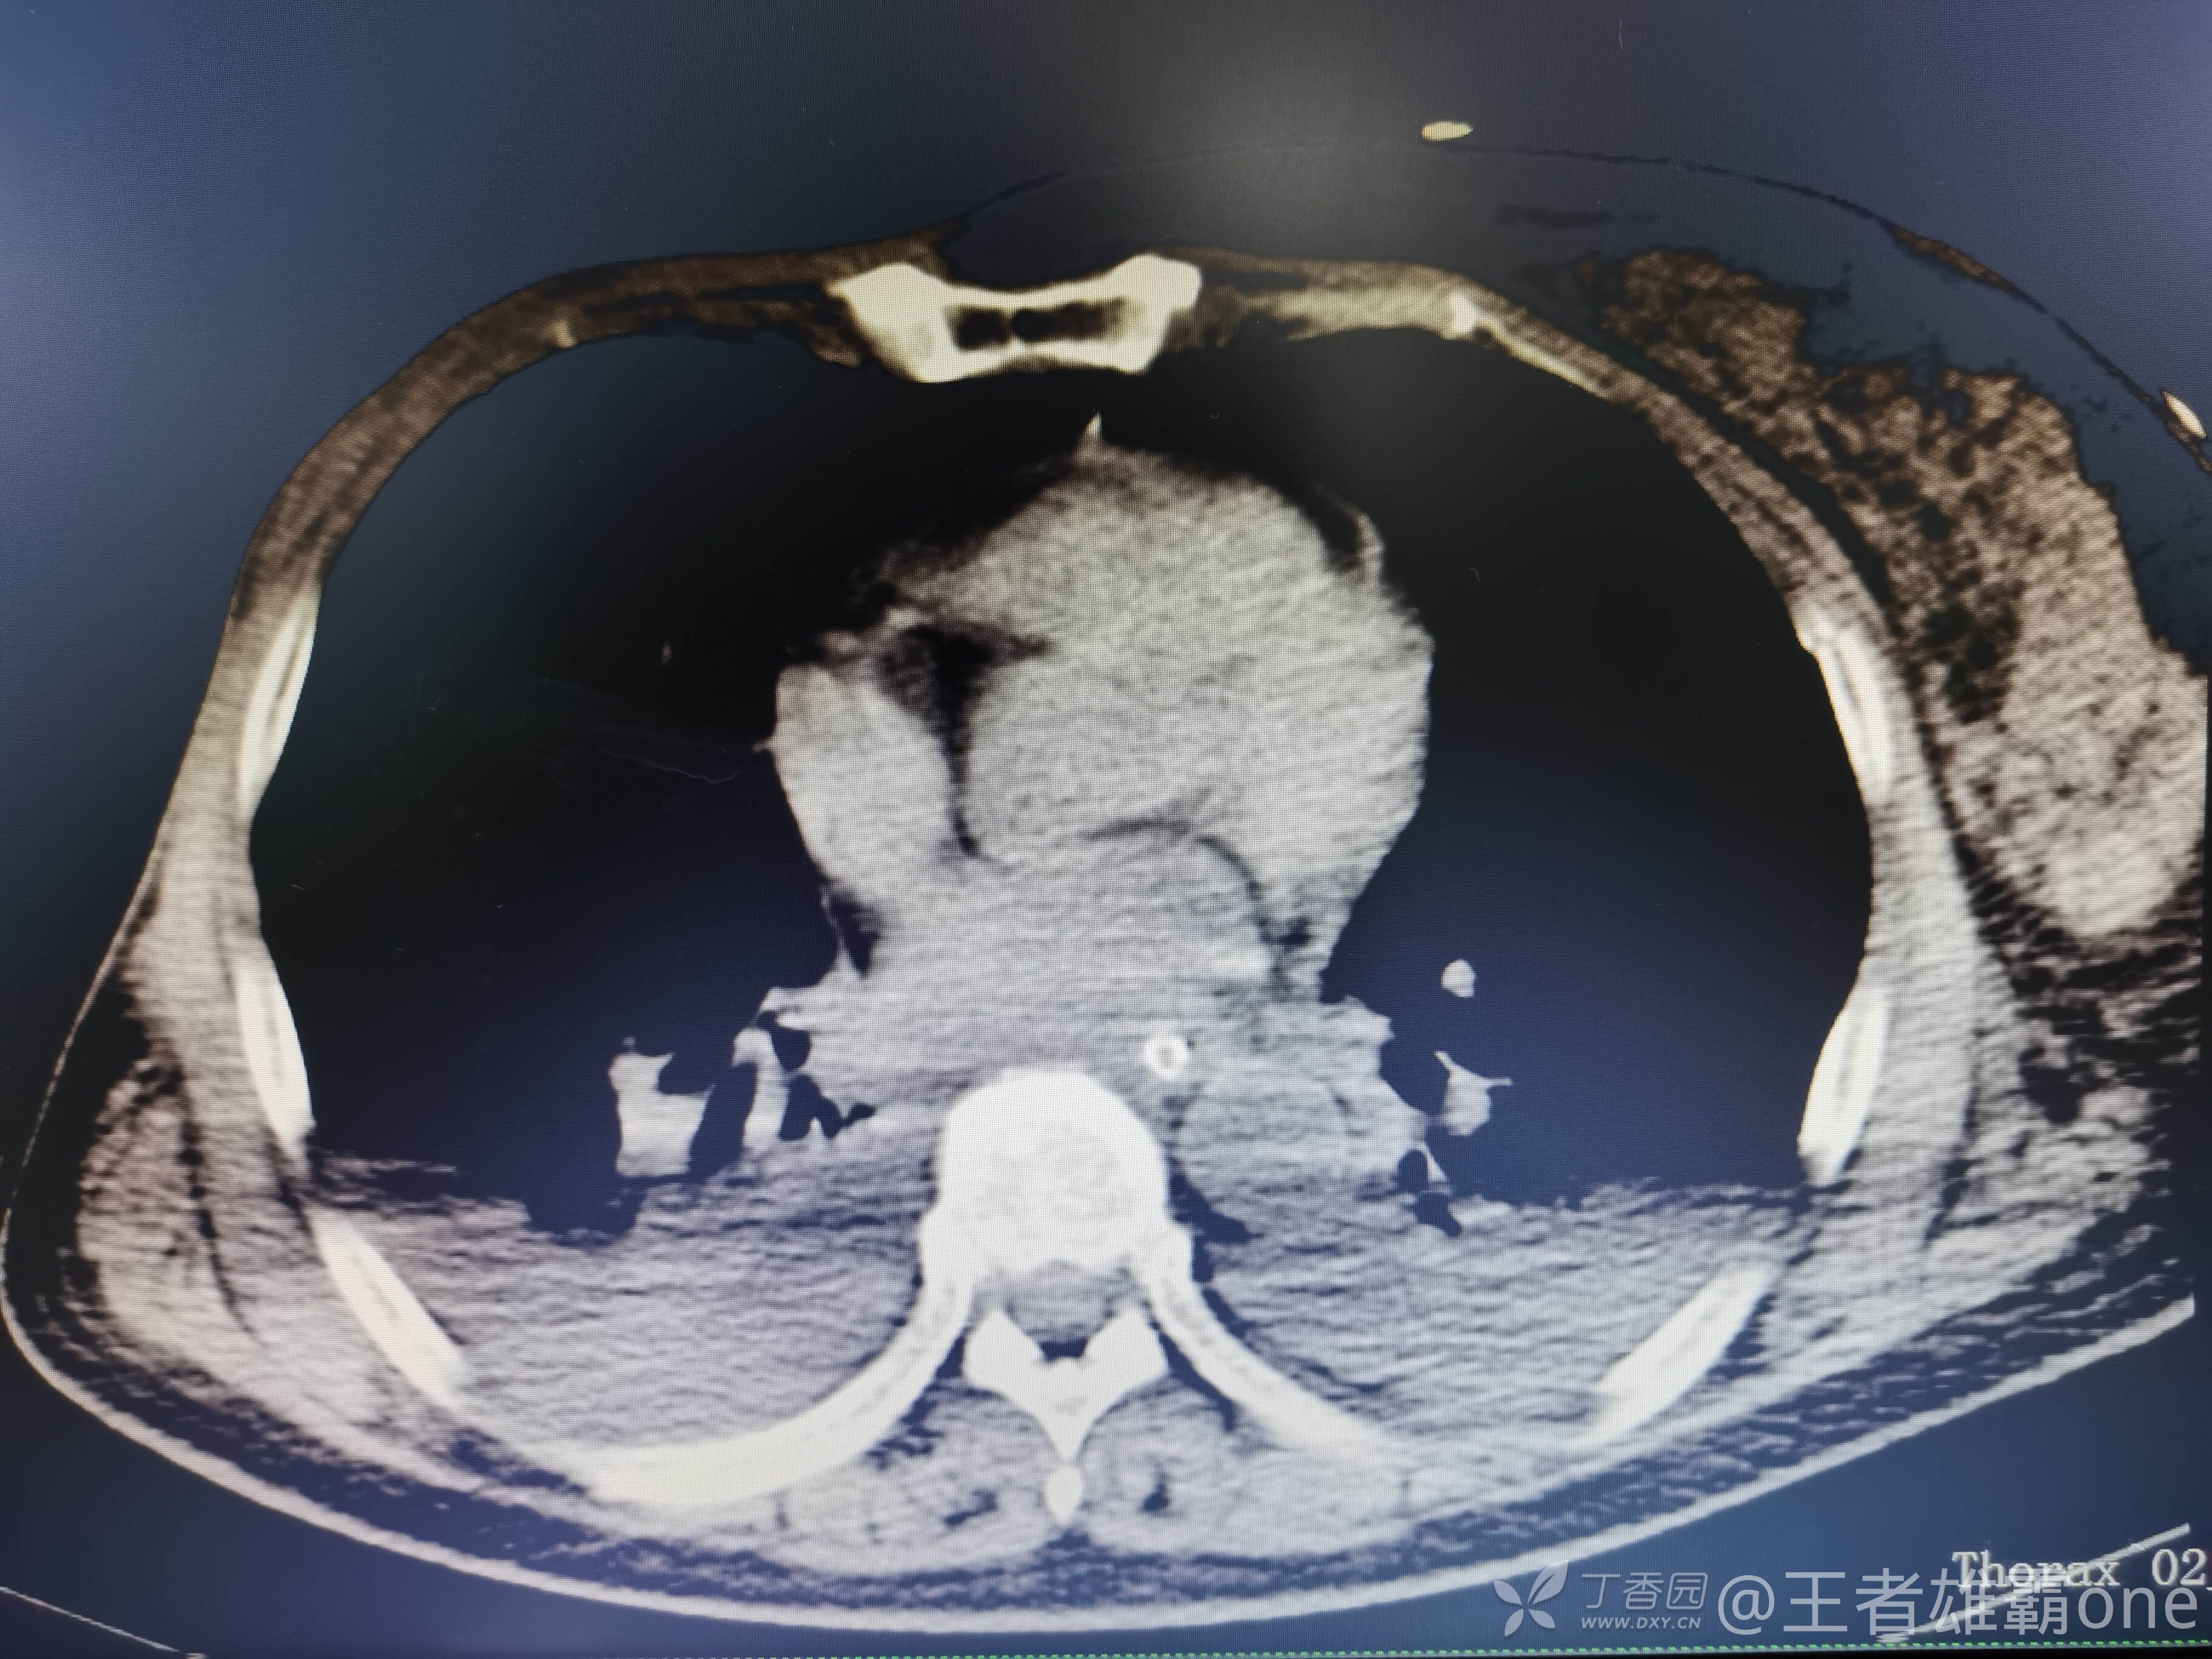

西门开心 推荐63岁女性,因车祸致短暂神志不清、多处疼痛4h入院。简单病史:伤后送至医院急诊就诊。完善头胸腹CT等检查,完善新冠核酸、血常规等化验。血常规提示血红蛋白62g/L。头颅CT提示未见明显外伤性改变。胸腹部CT视频见下:

收入院治疗期间,患者神志清晰,体温、血压、心率等生命体征基本正常,到了凌晨02 :00左右出现呼吸明显急促(呼吸频率30次/分以上),改面罩高浓度吸氧,血气提示氧分压57mmHg,二氧化碳分压37mmHg,乳酸4.4mmol/L,血红蛋白10.4g/dL。查急诊胸片:

那么问题来了,出现呼吸衰竭气管插管的病因是?请大家讨论分析!